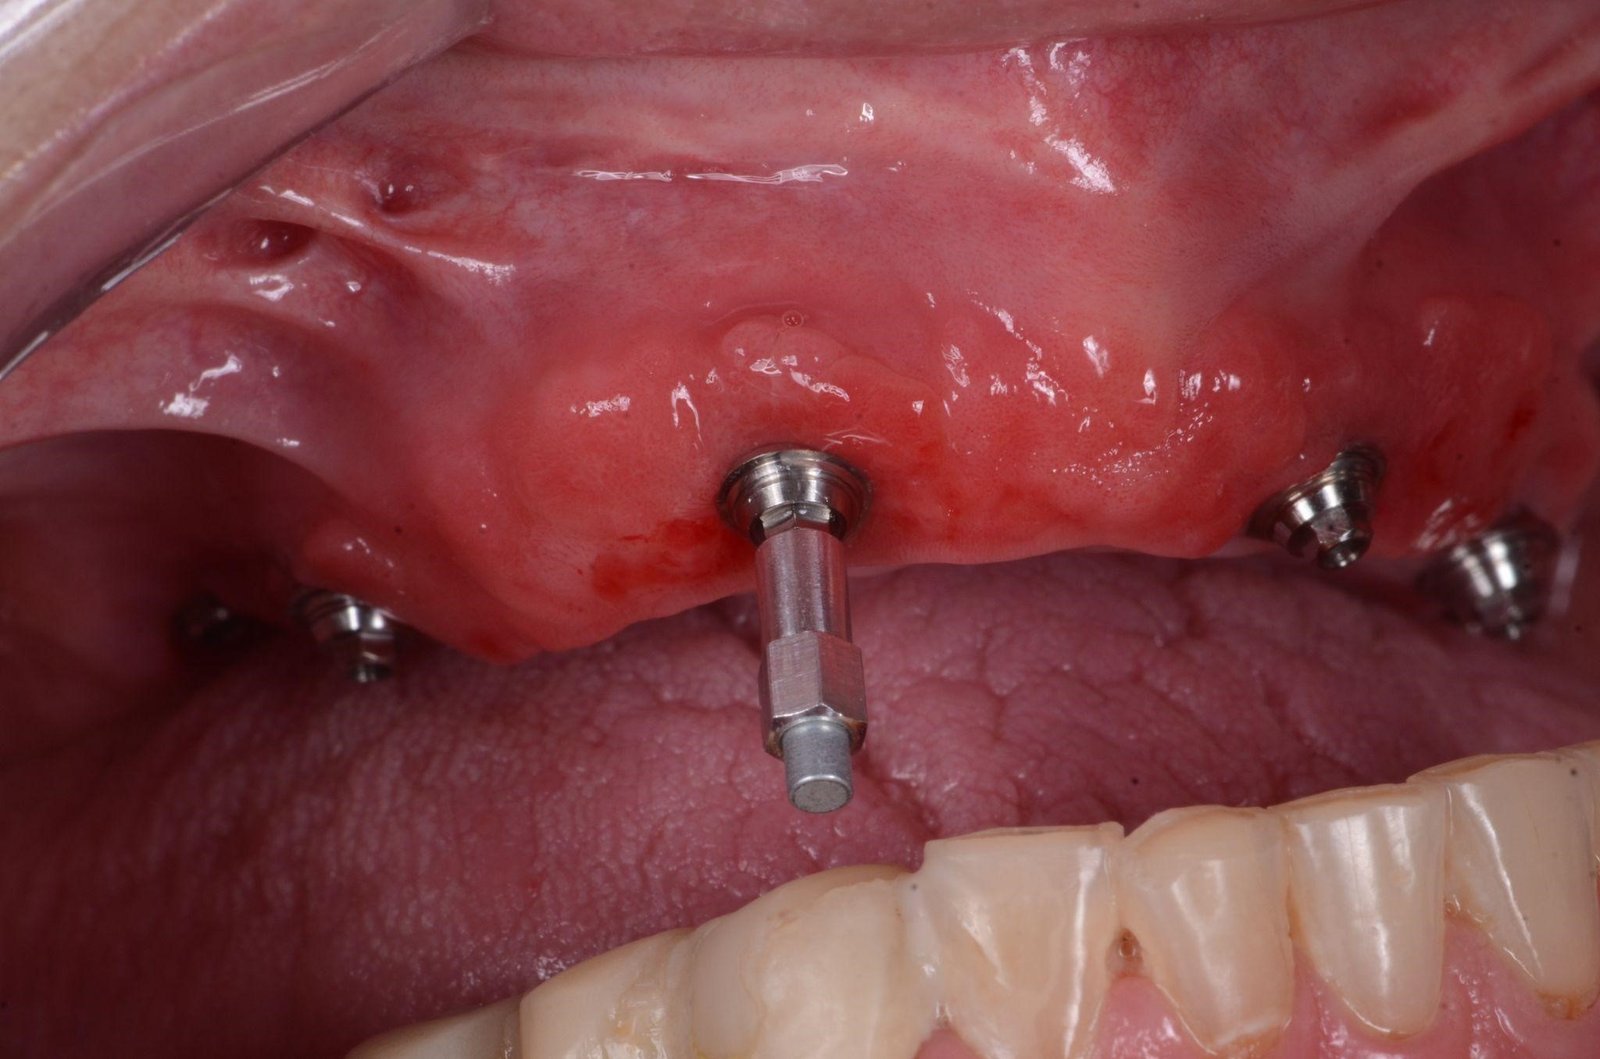

Este aparelho utiliza uma medida para indicar a estabilidade: o ISQ – Quociente de Estabilidade do Implante. Com este equipamento, pode-se ter o acompanhamento da evolução da estabilidade mecânica primária para a estabilidade biológica secundária, inclusive para confirmar o seu carregamento antecipado. O valor ISQ objetivo e numérico é obtido através da irradiação eletromagnética de um SmartPeg, uma peça de alumínio com um imã na ponta, que é aparafusado no hexágono/conexão externa ou hexágono/conexão interna do implante, dependendo do tipo de conexão do implante em questão. Figuras 3, 4 e 5.

– Sempre realizar a medição logo após a instalação do implante.

– Para isso, selecionar o correto SmartPeg para o tipo de implante utilizado.

– Com o montador do SmartPeg (Fig. 5), aparafusar o SmartPeg com força manual (4-6 N.cm) no implante.

– Colocar um protetor de biossegurança no Osstell Beacon.

– Posicionar a ponta do Osstell próxima da ponta do SmartPeg e realizar de forma automática a obtenção do valor ISQ na direção BL, e após, na direção MD.

– Após a mensuração logo após a instalação do implante, avaliar os valores de ISQ encontrados e decidir a carga de acordo com as recomendações da literatura (ver Fig.7).